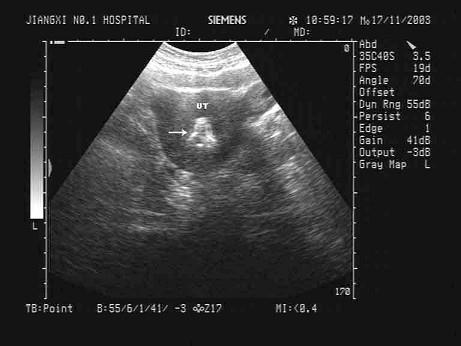

中年女性,中下腹横切面如图,箭头所示为?(?)A.子宫钙化环B.宫内节育器C.子宫肌瘤D.孕囊E.子宫肌瘤钙化

问题 中年女性,中下腹横切面如图,箭头所示为?(?)

选项 A.子宫钙化环 B.宫内节育器 C.子宫肌瘤 D.孕囊 E.子宫肌瘤钙化

答案 B